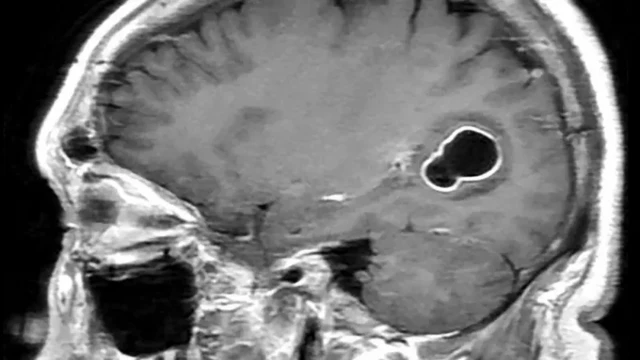

Likitoci sun gano fararen tsutsotsi wato 'tapeworms' a cikin kwakwalwar wani mutum da ke fama da matsanancin ciwon kai na ɓangare ɗaya da ake kira da 'Migraine'.

Likitocin sun yi masa hoton kwakwalwa inda suka gano farar tsutsa da ke haddasa cutar 'cysticercosis'.

Bayyanar irin waɗannan ƙuraje a kwakwalwa ana kiran su da 'neurocysticercosis'.